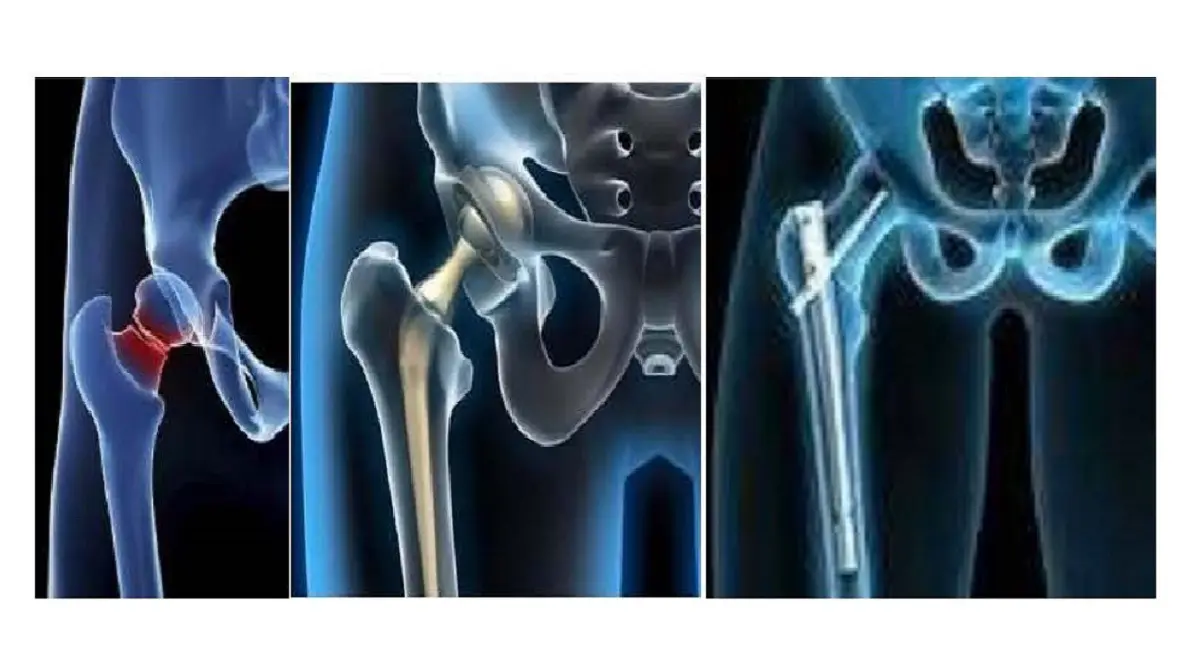

El tratamiento de las fracturas de cadera es quirúrgico (salvo alguna contraindicación importante), y el tipo de cirugía dependerá de dónde se localice la fractura.

«Están las fracturas que ocurren dentro de la cápsula articular de la cadera (intracapsulares, fracturas del cuello de fémur, subcapitales, basicervicales), cuyo tratamiento quirúrgico es una prótesis total o parcial de cadera y en algunos casos, si la fractura no tiene desplazamiento y hay buena calidad ósea se realiza una osteosíntesis, es decir, un sistema de fijación con tornillos canulados. Y las fracturas que se localizan por debajo de la cápsula articular (pertrocantéreas y subtrocantéreas), y su tratamiento es fijar la fractura conservando su cabeza del fémur (clavos intramedulares, tornillo-placa, etc.)»